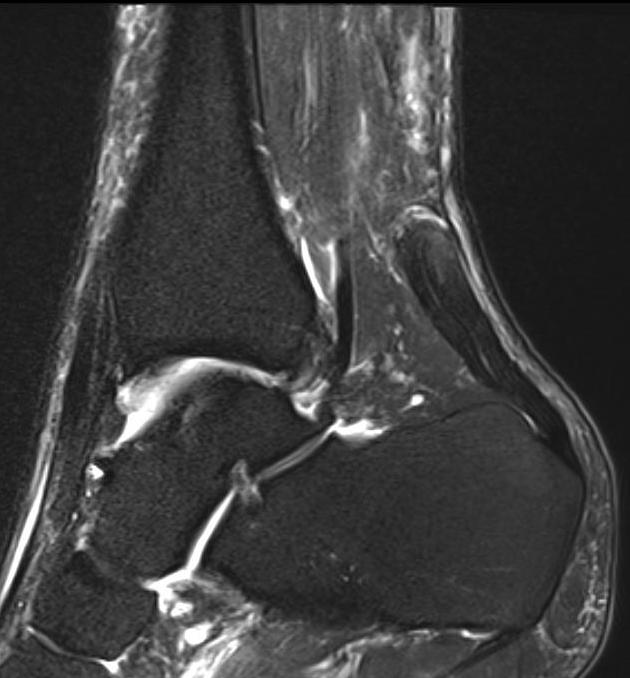

MRI

Indication

- incomplete rupture / clinical uncertainty

- chronic tears - measurement of gap for reconstruction planning

Chronic retracted